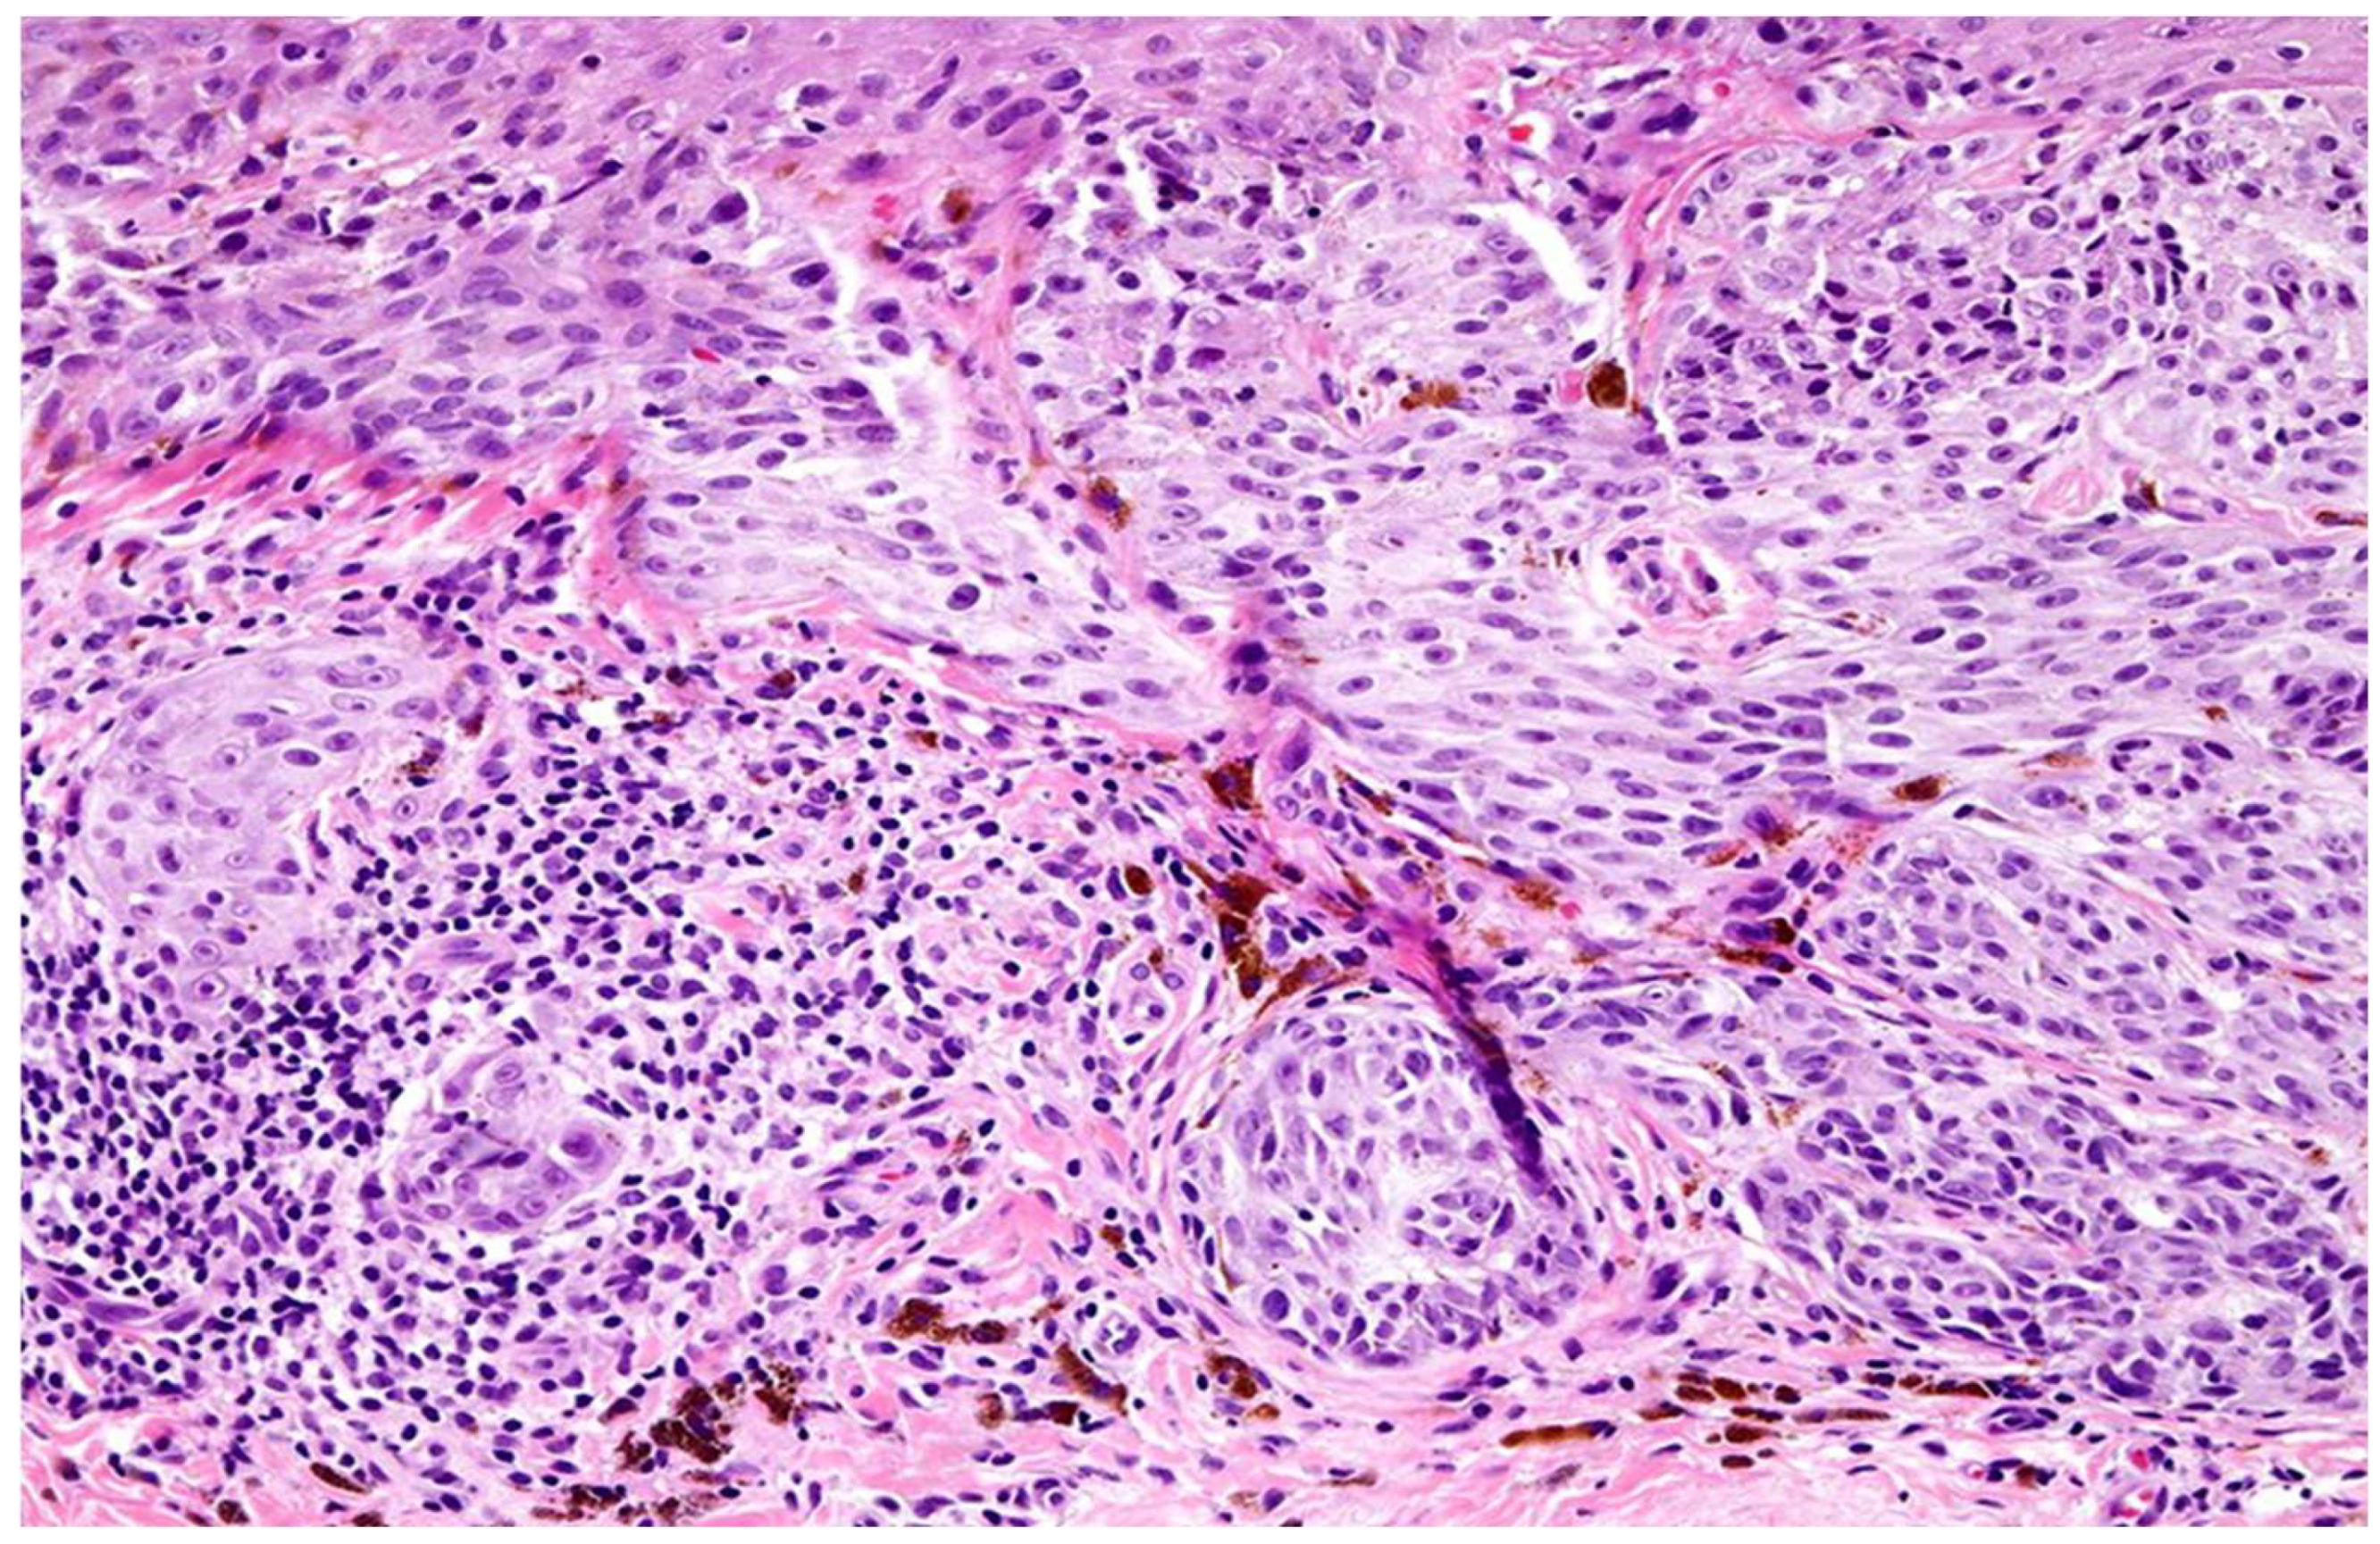

Histopathological assessment of TILs was performed on hematoxylin and eosin (H&E)-stained sections. TILs were classified according to the American Association for Cancer Research (AACR) guidelines into three distinct categories (Figure 1): brisk, non-brisk, and absent. Brisk TILs were defined as continuous, dense lymphocytic infiltrate encompassing more than 50% of the tumor perimeter and/or diffusely infiltrating tumor cell nests. Non-brisk TILs were characterized by focal or patchy infiltrates involving less than 50% of the tumor perimeter or scattered infiltration among tumor cells. Absent TILs were determined by the near-complete lack of lymphocytic infiltration within or around tumor cell nests, excluding perivascular lymphocytes or those confined to the fibrous septae.

Figure 1.

Morphological patterns of tumor-infiltrating lymphocytes (TILs) according to the AACR classification tool. (A) Brisk TIL histological section showing dense peri-tumoral lymphocytic infiltration closely applied around the tumor perimeter (arrows). (B) Brisk TIL schematic representation demonstrating peri-tumoral lymphocytes with variable intra-tumoral extension. (C) Non-brisk TIL histological section showing patchy or focal lymphocytic infiltration along parts of the tumor perimeter (arrowhead). (D) Non-brisk TIL schematic representation illustrating incomplete peri-tumoral coverage by lymphocytes. (E) Absent TIL histological section and schematic showing lack of appreciable lymphocytic infiltrate at the tumor–stroma interface.

From an initial pool of 385 archived primary cutaneous melanoma cases diagnosed between 2020 and 2024, 205 samples were selected based on predefined inclusion and exclusion criteria. Tumor-infiltrating lymphocytes (TILs) were classified into brisk (n = 65), non-brisk (n = 60), and absent (n = 80) categories by three senior pathologists according to the AACR guidelines (Figure 2). Inter-rater reliability was assessed using intra-class correlation coefficients (ICC), yielding values of 0.90 and 0.95 for brisk and absent TILs, respectively, indicating excellent agreement. Discordant cases were resolved by averaging the scores from two pathologists in agreement (Table 1).

Melanoma tumor infiltrating lymphocytes, light micrograph. Tumor-infiltrating lymphocytes (TILs) in melanoma, showing a dense lymphocytic infiltrate within and around the melanoma, appear to correlate with a better prognosis; brisk TILs are present throughout the vertical growth phase or across. Original magnification ×20.

Among the brisk TIL cases, 11 samples exhibited absent TNF-α staining by immunohistochemistry (IHC), and six showed absent IFN-γ staining despite histologic evidence of immune infiltration. This discordance suggests potential post-translational modification or suppression of cytokine protein expression within the tumor microenvironment (TME).